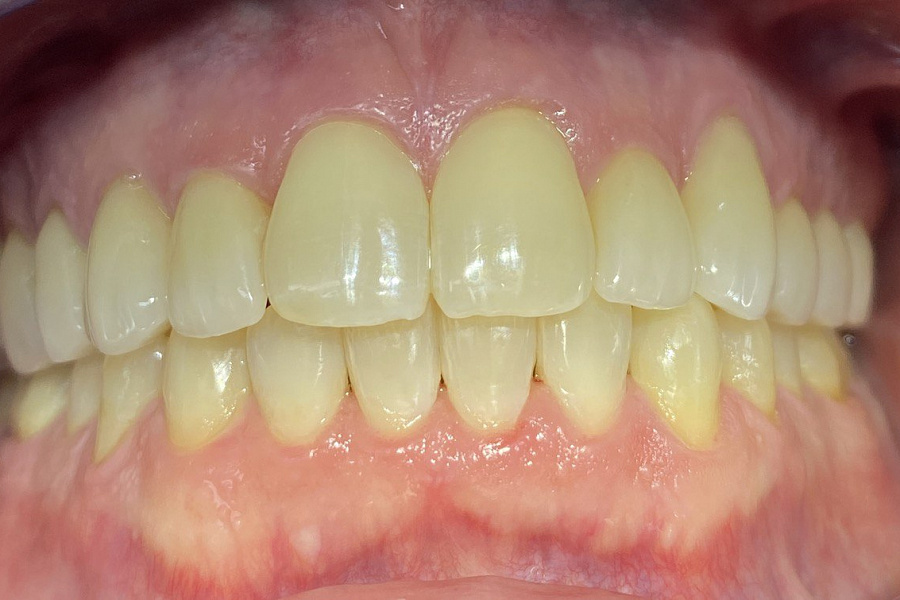

Ортодонтическое лечение с помощью элайнеров длилось 10 месяцев. Далее последовало протезирование и установка виниров.

Результат лечения